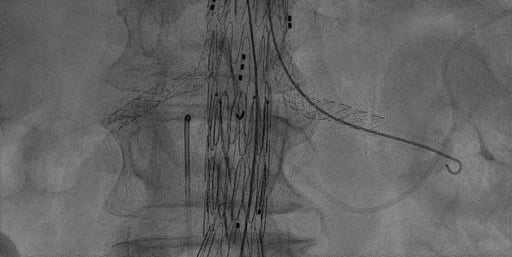

ENDOPROTESI AORTICA PERCUTANEA

Endoprotesi aortica percutanea: si tratta del trattamento percutaneo, attraverso le arterie femorali, degli aneurismi (dilatazioni) dell'aorta, nel suo decorso nell'addome. E' una metodica utilizzata in pazienti non idonei alla chirurgia.